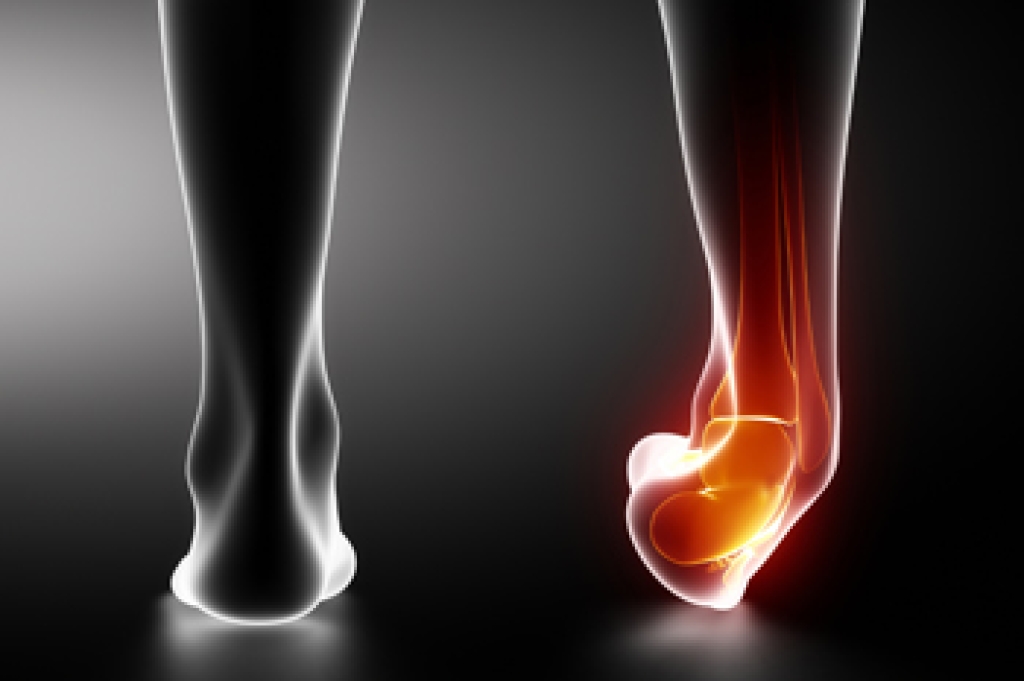

The Proper Healing of a Broken Ankle

Proper healing of a broken ankle requires timely medical attention, effective treatment, and careful rehabilitation. Treatment depends on the severity of the fracture. For minor fractures, non-surgical options like casting or using a walking boot may be sufficient to immobilize the ankle, allowing the bone to heal. More severe fractures, where the bone is misaligned or displaced, often require surgery using screws or plates to stabilize the bone. During recovery, rest and elevating the ankle can help to reduce swelling. Using crutches or a walker prevents putting weight on the ankle until cleared by a doctor. Targeted exercises play a critical role in regaining strength, mobility, and balance after the bone heals. Full recovery can take several weeks to months, depending on the injury's severity. If you have broken your ankle, it is strongly suggested that you visit a podiatrist as quickly as possible for a proper diagnosis and medical advice.

Broken ankles need immediate treatment. If you are seeking treatment, contact Kellvan Cheng, DPM from Elite Foot & Ankle. Our doctor can provide the care you need to keep you pain-free and on your feet.

Broken Ankles

A broken ankle is experienced when a person fractures their tibia or fibula in the lower leg and ankle area. Both of these bones are attached at the bottom of the leg and combine to form what we know to be our ankle.

When a physician is referring to a break of the ankle, he or she is usually referring to a break in the area where the tibia and fibula are joined to create our ankle joint. Ankles are more prone to fractures because the ankle is an area that suffers a lot of pressure and stress. There are some obvious signs when a person experiences a fractured ankle, and the following symptoms may be present.

Symptoms of a Fractured Ankle

- Excessive pain when the area is touched or when any pressure is placed on the ankle

- Swelling around the area

- Bruising of the area

- Area appears to be deformed

If you suspect an ankle fracture, it is recommended to seek treatment as soon as possible. The sooner you have your podiatrist diagnose the fracture, the quicker you’ll be on the way towards recovery.